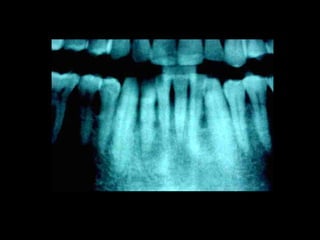

La periodontitis, denominada comúnmente piorrea, es una enfermedad que

inicialmente puede cursar con gingivitis, para luego proseguir con una pérdida de

inserción colágena, recesión gingival, e incluso la pérdida de hueso, en el caso de

no ser tratada, dejar sin soporte óseo al diente. La pérdida de dicho soporte

implica la pérdida irreparable del diente mismo.

De etiología bacteriana que afecta al periodonto (el tejido de sostén de los dientes,

constituido por la encía, el hueso alveolar, el cemento radicular y el ligamento

periodontal) se manifiesta más comúnmente en adultos mayores de 35 años, pero

puede iniciarse en edades más tempranas.